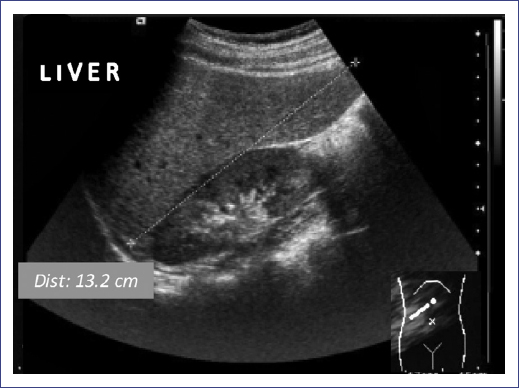

Later, he turned to the service reporting fatigue and a low growth velocity rate (Fig. 2). Laboratory tests showed abnormal liver function and lipid profile (Fig. 4). Due to the evolution of the patient, treatment with somatotropin was resumed.

IGF-1 levels were found within the normal range during the treatment with GH (152 ng/ml, −1.3 SDS at age 12 and 210.7 ng/ml, −0.49 SDS at age 13). At present, the patient reports good general condition: growth rate is recovering, the puberty started (Tanner 2), and transaminases and lipid profile have reached normal values (Fig. 4) with the resolution of hepatic steatosis on ultrasound (Fig. 5). At present, at 14 years of age, no recurrence of thyroid cancer has appeared 9 years after diagnosis and 4 years after the start of GH therapy. The last thyroid gammagram with 131I was considered within the standard limits and no data suggestive of residual thyroid tissue and undetectable TSH-stimulated thyroglobulin (with negative Ab antithyroglobulin). At present, the patient continues with levothyroxine treatment, Vitamin D and GH and undergoes routine examinations for cancer follow-up and hormonal replacement.